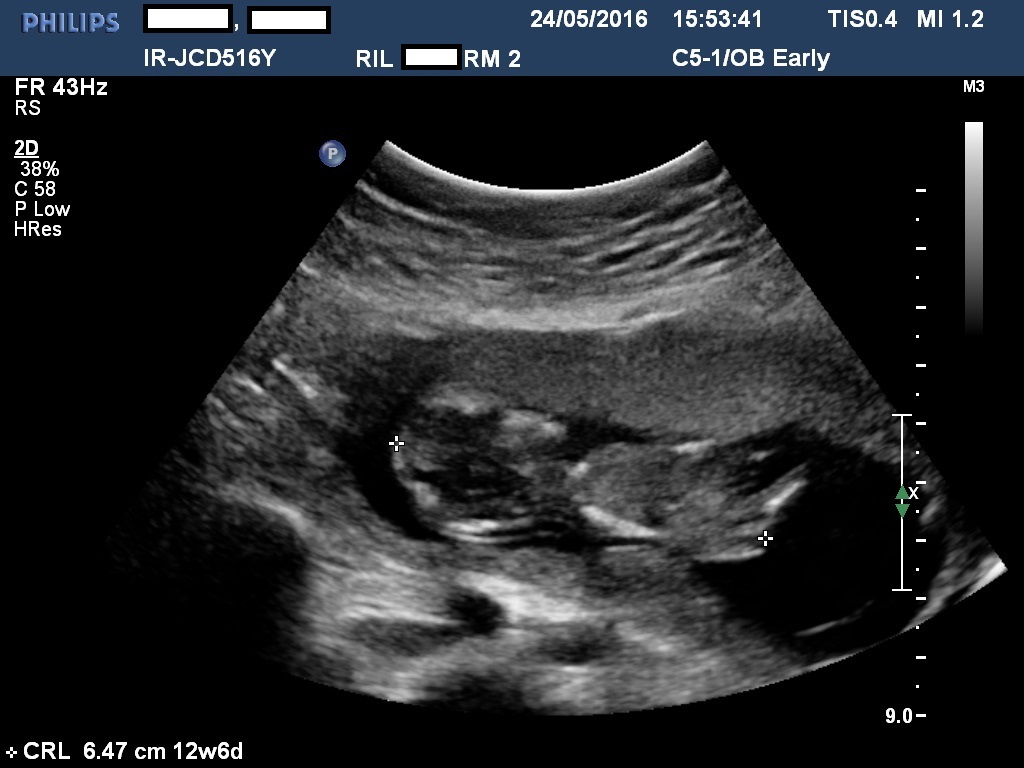

Can someone help me determine if this is a girl or a boy based on the nub theory. I seem to be struggling with the photos. Thank you in advance! :)Attachment 31797Attachment 31798Attachment 31799

I think girl from last pic. I think I see the end of a girly nub behind the sonographer's cross.